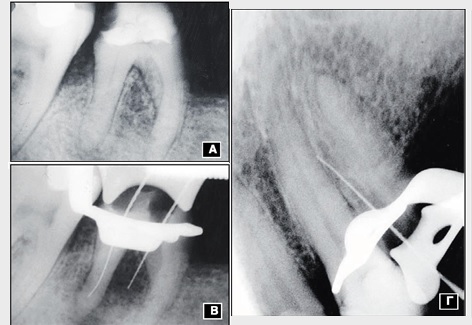

Εικ. 3: Αποτυχία της άμεσης κάλυψης του πολφού σε άτομο μέσης ηλικίας. Α. Ακτινογραφική εικόνα του 36, όπου φαίνεται η δευτερογενής τερηδόνα κάτω από μια έμφραξη αμαλγάματος. Ο πολφός ήταν ζωντανός χωρίς κλινικά συμπτώματα, ενώ παρατηρείται ενασβεστίωση του μυλικού θαλάμου.

Β. Δύο χρόνια μετά την άμεση κάλυψη του πολφού και την αντικατάσταση της έμφραξης. Οι δοκιμασίες ζωτικότητας είναι αρνητικές και στο ακτινογράφημα εμφανίζονται περιακρορριζικές αλλοιώσεις στην εγγύς και άπω ρίζα του γομφίου.

Eικ. 8: Διάτρηση κατά τη διάνοιξη λόγω ενασβεστίωσης.

Α. Γομφίος της κάτω γνάθου με μεγάλη καταστροφή της μύλης και ενασβεστίωση των εγγύς ριζικών σωλήνων.

Β. Διάτρηση του υποπολφικού τοιχώματος κατά τη διάρκεια του εντοπισμού των στο¬μίων των εγγύς ριζικών σωλήνων.

Γ. Διάτρηση πλάγιου τοιχώματος σε προγόμφιο της άνω με ενασβεστίωση του μυλικού θαλάμου και του ριζικού σωλήνα.